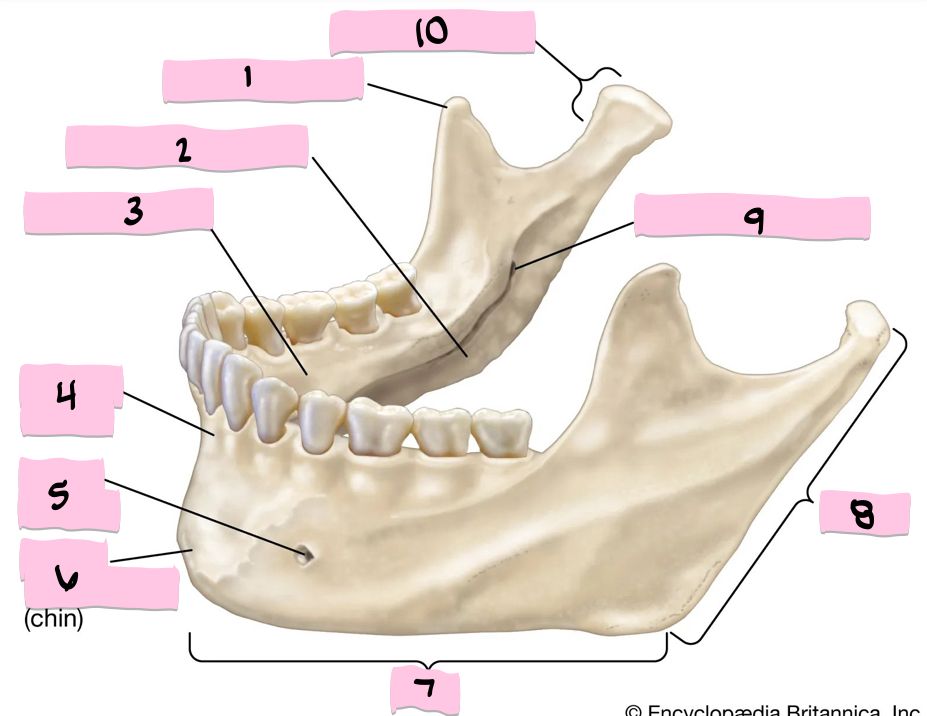

What is 1 pointing to?

Coronoid process

What is 2 pointing to?

Submandibular fossa

What is 3 pointing to?

Sublingual fossa

What is 4 pointing to?

Alveolar process

What is 5 pointing to?

Mental foramen

What is 6 pointing to?

Mental protuberance

What is 7 pointing to?

Body

What is 8 pointing to?

Ramus

What is 9 pointing to?

Mandibular foramen

What is 10 pointing to?

Condylar process